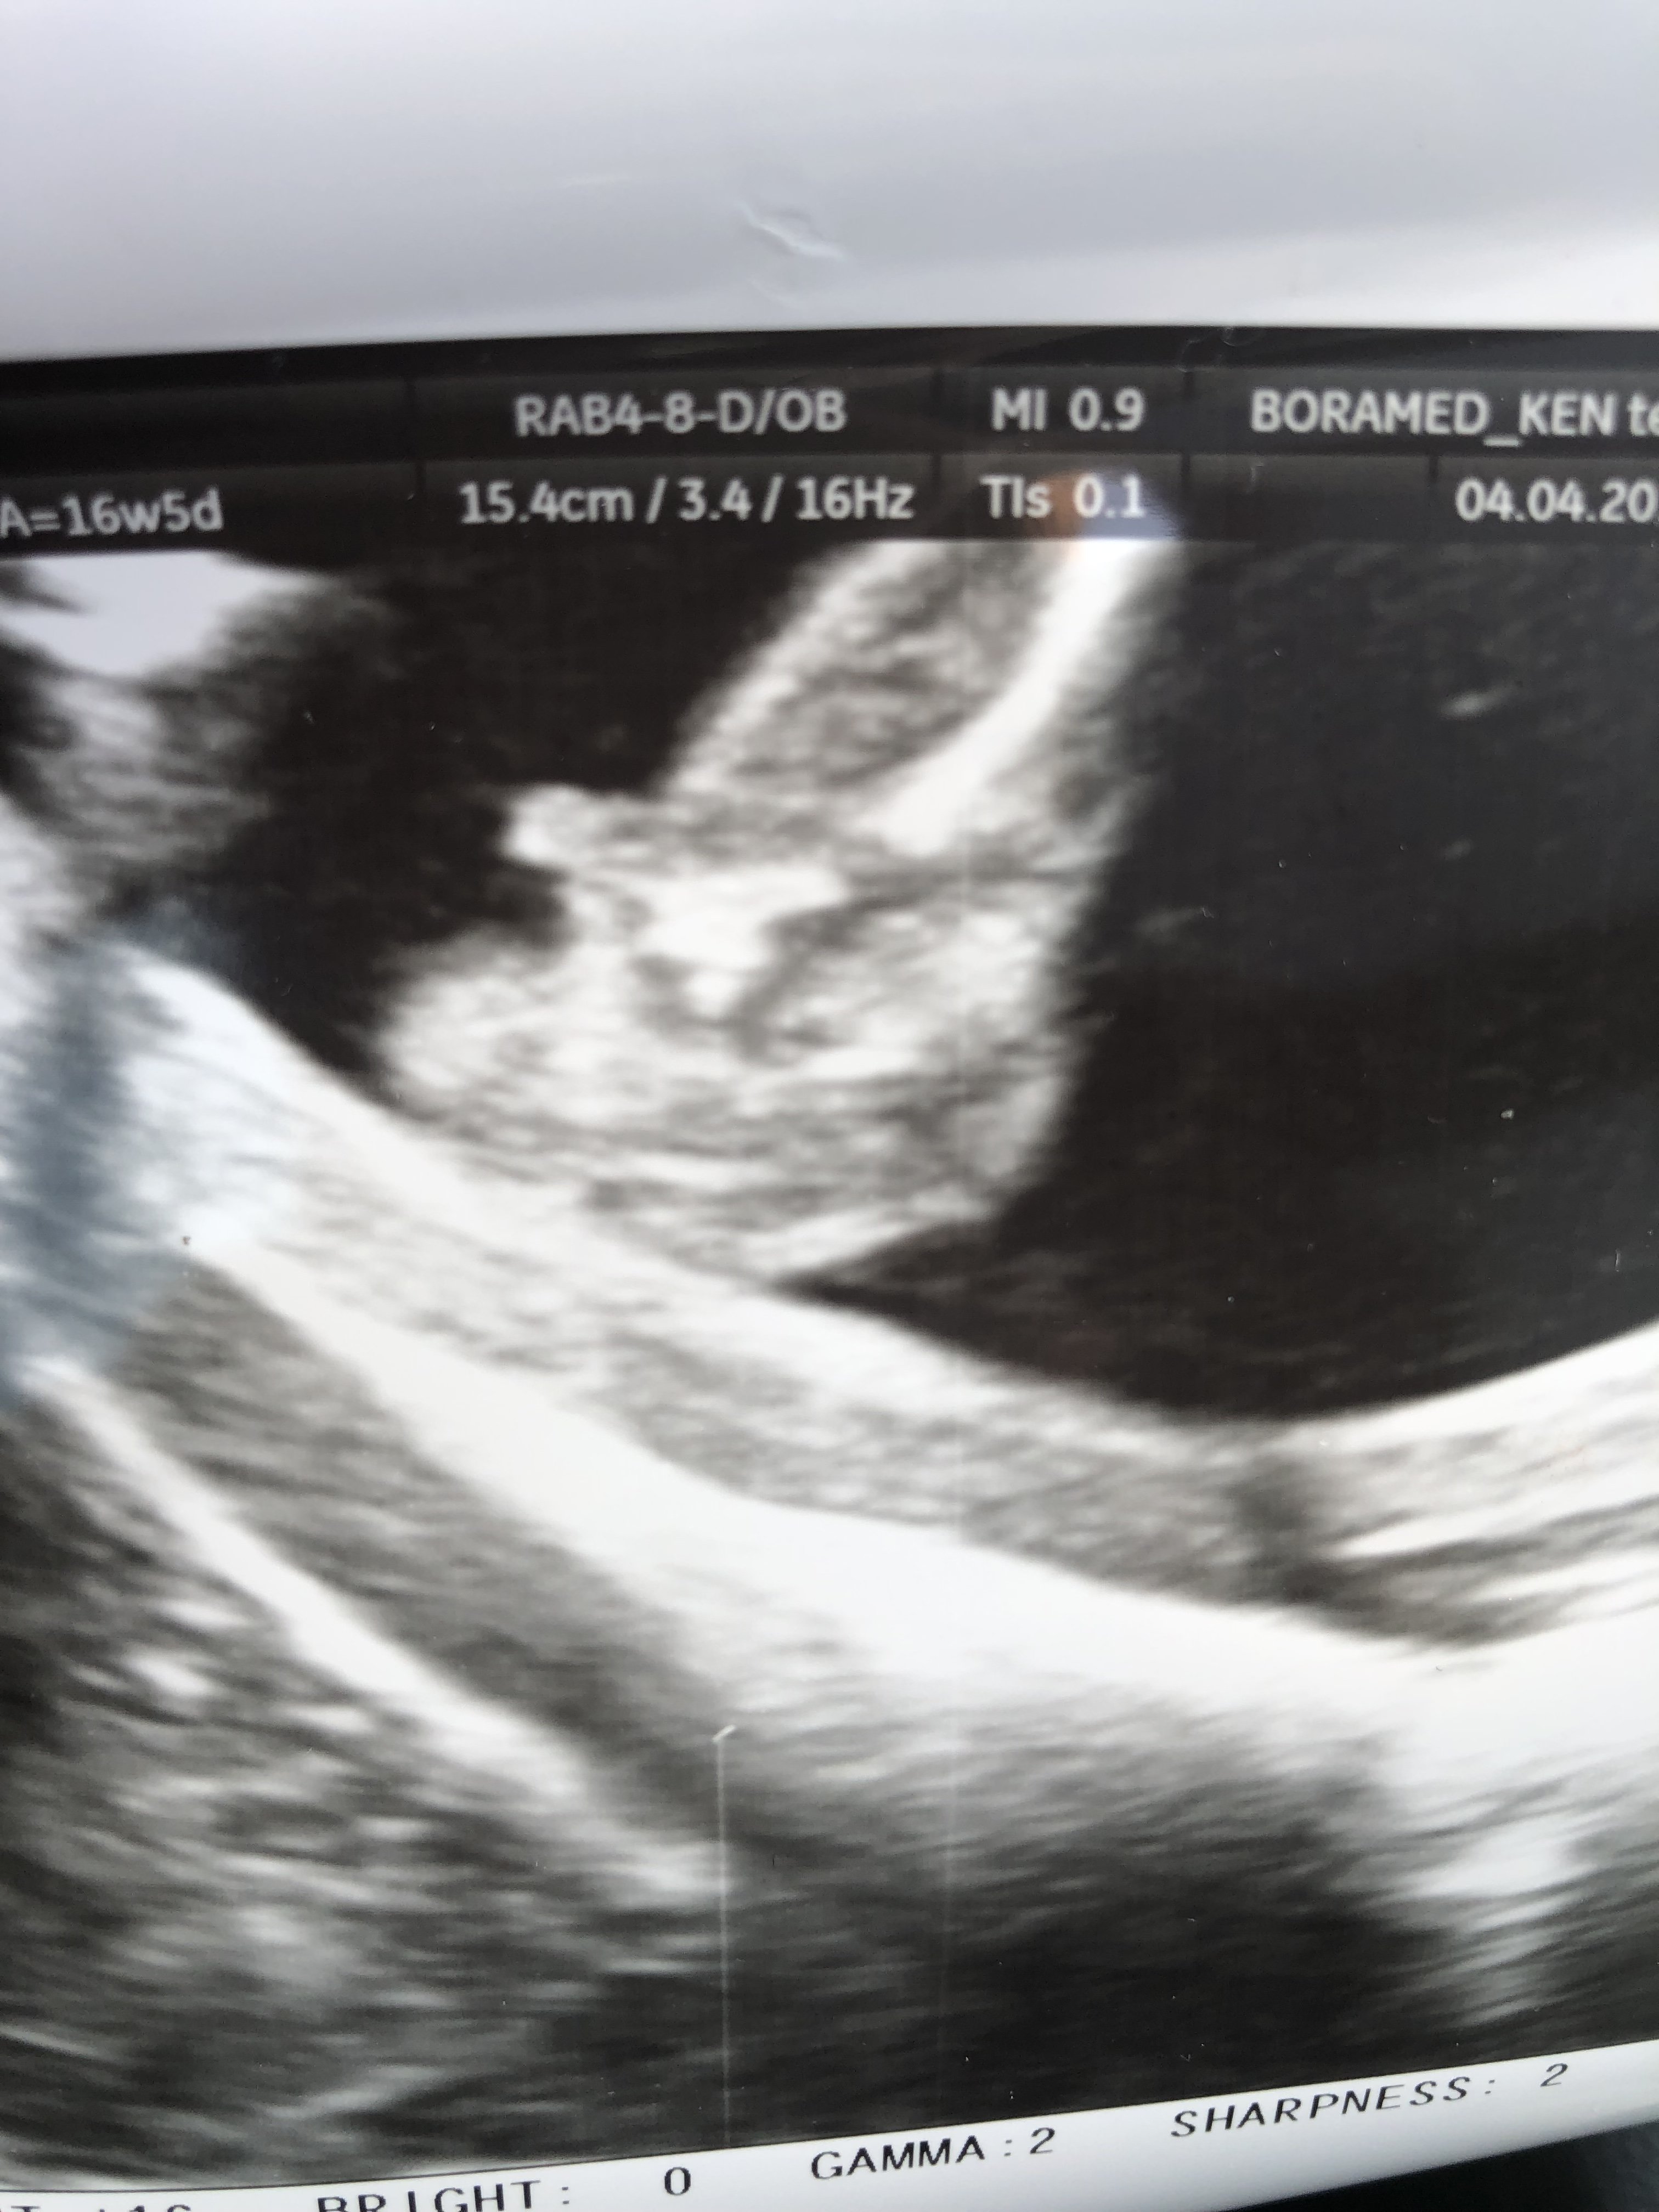

Cześć dziewczyny, dzisiaj byłam u ginekologa który z 90% pewnością stwierdził ze nosze pod sercem synka, później dzidziuś przeskakiwał i się wyginał i ciężko było coś uchwycić, dziwnie mam wrażenie ze obydwa zdjęcia które otrzymałam jednak się różnią.

Co myślicie, chłopak ?

• E366374C-7946-46C8-87A2-0BC7238E0BF5.jpeg

E366374C-7946-46C8-87A2-0BC7238E0BF5.jpeg

895,5 KB · Wyświetleń: 489